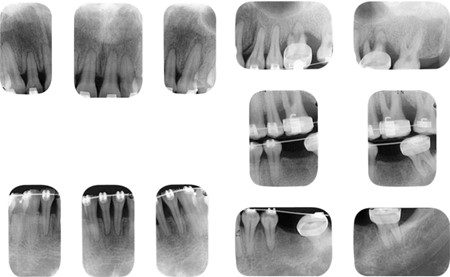

Chuyển động chỉnh nha có thể là yếu tố khởi phát quá trình tiêu chân răng ở những răng bị chấn thương nặng trước đó (hình 1-34).

Hai bệnh lý răng miệng phổ biến nhất là sâu răng và bệnh nha chu. Trong đó, bệnh nha chu thường gặp hơn ở nhóm bệnh nhân người lớn. Do đó, tất cả các răng cối lớn ở bệnh nhân trưởng thành nên được thăm dò trên mọi bề mặt. Việc thăm dò bổ sung sẽ tùy thuộc vào mức độ tổn thương nha chu của các răng sau hoặc dựa vào bằng chứng trên phim X-quang.

Tác động có hại của các lực chấn thương lên răng bị bệnh nha chu đã được ghi nhận rõ ràng trong nhiều nghiên cứu (hình 1-41).

Lực chỉnh nha đã được chứng minh là có thể gây ra các tổn thương tương tự lên cấu trúc nâng đỡ răng khi có bệnh nha chu đang hoạt động. Do đó, trước khi bắt đầu điều trị chỉnh nha, bác sĩ lâm sàng cần đảm bảo không có bệnh lý nào đang hoạt động và điều kiện sức khỏe răng miệng tối ưu.

Sâu răng – bệnh lý răng miệng phổ biến khác – thường gặp hơn ở thanh thiếu niên so với người lớn. Tuy nhiên, tất cả bệnh nhân già trẻ đều cần được tầm soát sâu răng cả trước và trong suốt quá trình điều trị chỉnh nha. Mọi tổn thương sâu răng hiện có cần được phục hồi và nếu có liên quan đến tủy, phải xử trí trước khi bắt đầu điều trị.

Đã có báo cáo nhiễm trùng trong ống tủy có thể gây tiêu chân răng khi có tác động bởi lực chỉnh nha. Ngoài ra, các răng đã được điều trị tủy trước đó cần được kiểm tra để đảm bảo trám bít tốt và không có dấu hiệu bệnh lý quanh chóp.